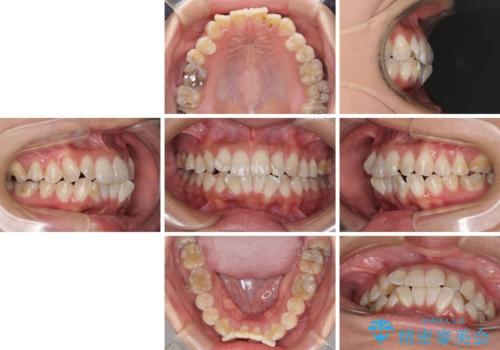

- 上下の前歯のでこぼこを気にして来院された患者様です。

職場の都合により、表側のワイヤー装置や着脱作業が頻繁なマウスピース矯正は困難とのことで、全く目立たない裏側矯正装置を用いて口元を整えることとしました。

途中転勤や出産があり、通院できない期間が長くありましたが、無事に歯列を整えることができました。